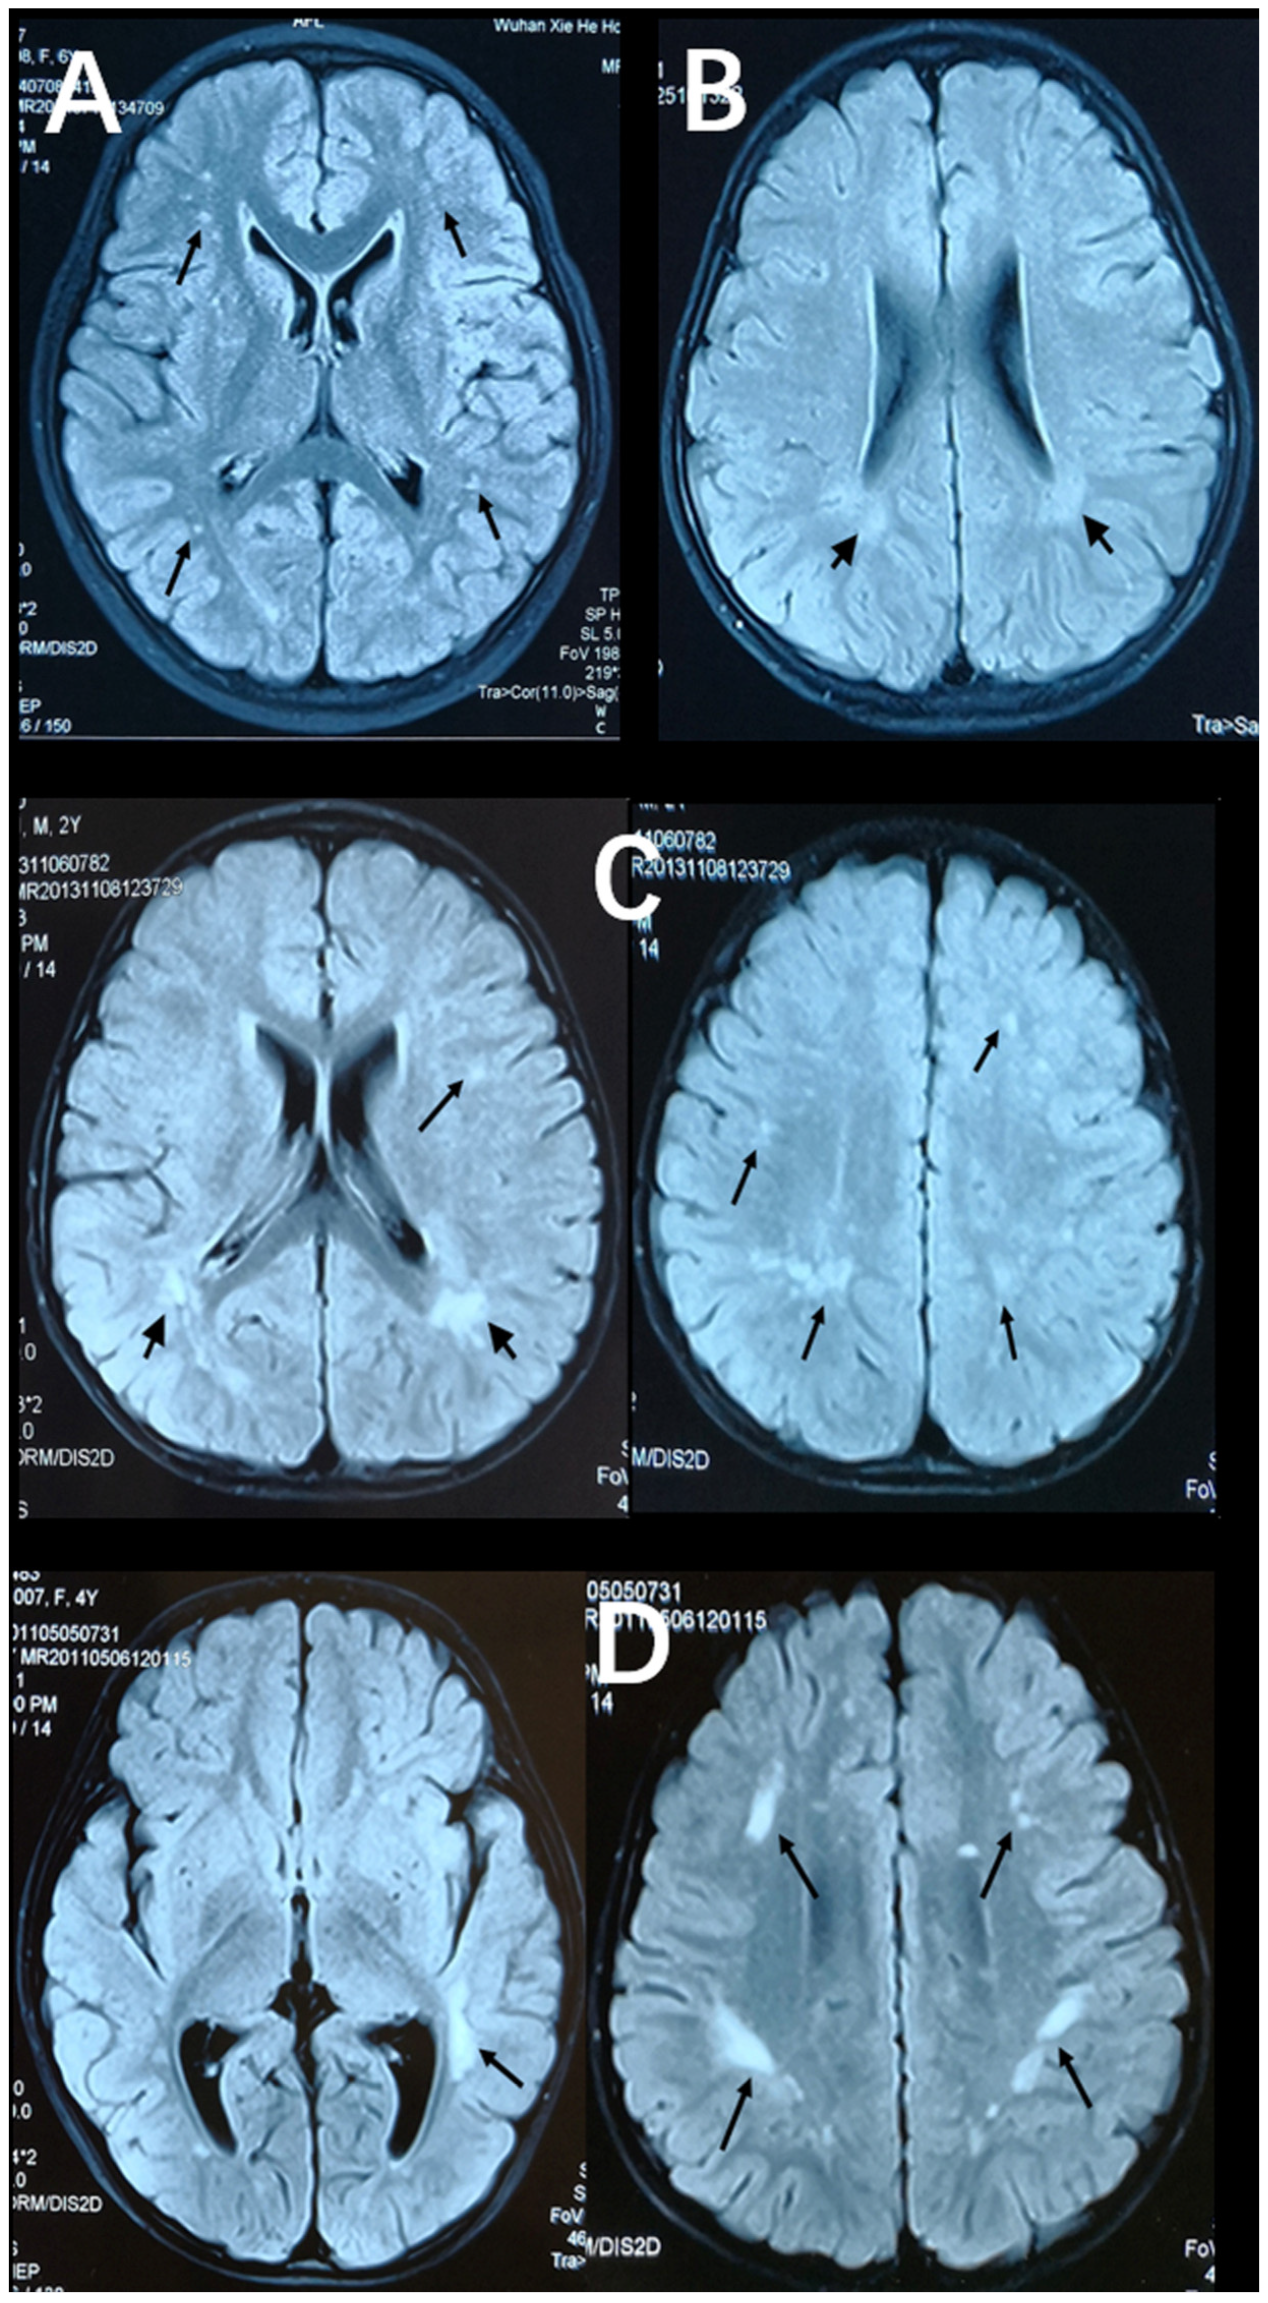

Figure 2 and Figure 3 show representative T2-FLAIR images with annotated Fazekas scores and involved areas. The numbers of participants with Fazekas scores of 1, 2, 3, 4, 5, and 6 were 15, 15, 2, 5, 4, and 2, respectively. PVH was detected in 25 participants and DWMH was detected in 32 participants. PVH and DWMH were detected concurrently in 14 participants. The frontal lobe (31/32) was the most frequently involved area of deep white matter, which was followed by the parietal lobe (22/32) and the occipital lobe (11/32). The temporal lobe (10/32) was the least involved area. Table 3 shows the distributions of Fazekas scores and involved areas.

Figure 3. Axial, T2-FlAIR cerebral MRI scans with annotated involved areas. (A) The frontal and occipital lobes involvement (black arrows). (B) Periventricular white matter involvement (short black arrows). (C) The frontal and parietal lobes involvement (black arrows) together with periventricular white matter involvement (short black arrows). (D) The temporal, frontal and parietal lobes involvement (black arrows).